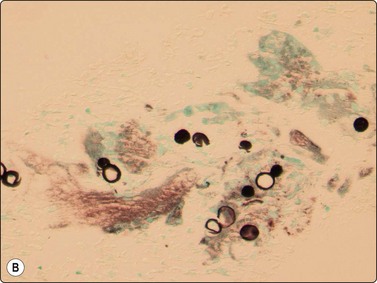

Sarcoidosis has distinctive rounded epithelioid granulomas infiltrated by lymphocytes without necrosis, but its diagnosis requires negative AFB stains, mycobacterial cultures and PCR with the correct clinical presentation and serology (Fig. 18.7).42

image image

Fig. 18.7 (A) Cohesive rounded sarcoid granuloma with occasional lymphocytes (Giemsa,

×400); (B) Rounded sarcoid granuloma (Pap, ×400).